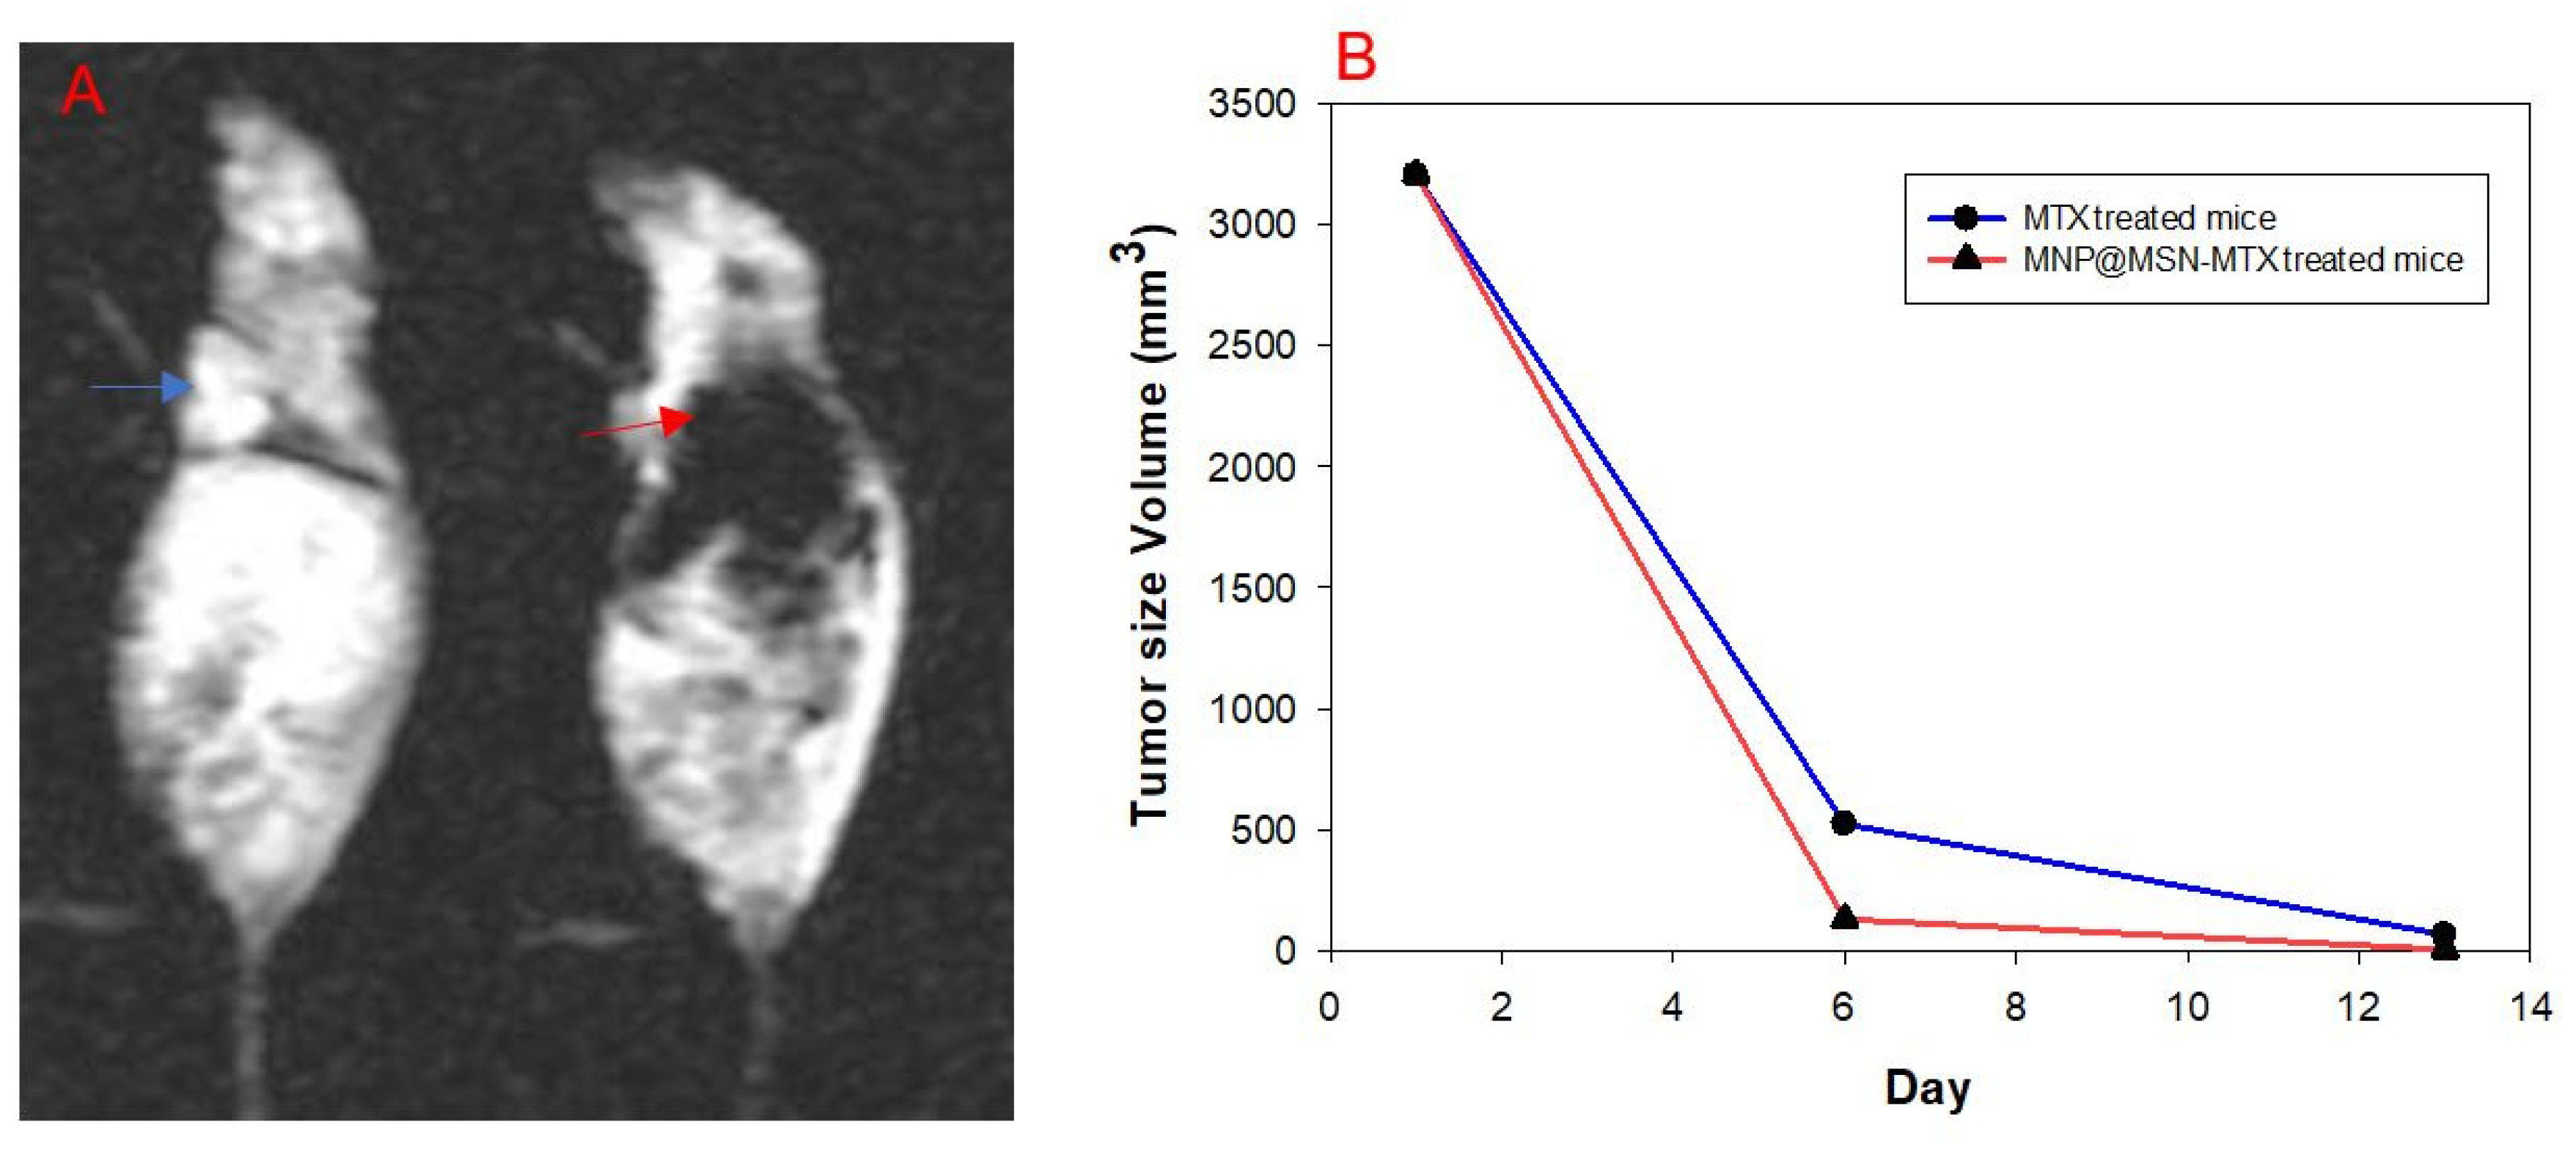

3.5. In Vivo Experiments and MRI Analysis